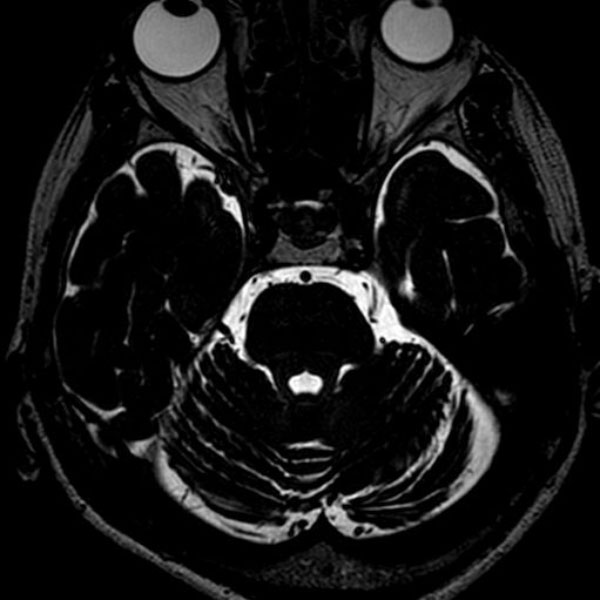

手術前

(MR1)